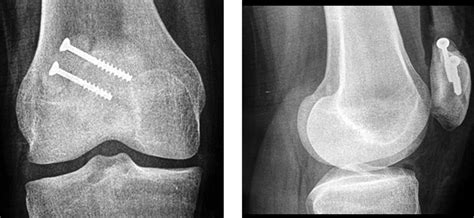

⚠️ Note: It is critical to differentiate between a symptomatic bipartite patella and a recent patellar fracture. Unlike a fracture caused by sudden trauma, a bipartite patella typically features smooth, rounded edges on the separated bone fragments, which can be clearly visualized on X-rays.

Diagnosis usually begins with a thorough physical examination, during which a healthcare professional will press on the kneecap to locate the exact point of tenderness. To confirm the diagnosis and rule out other potential causes of knee pain, imaging studies are essential:

X-Ray The primary tool to visualize the separation in the bone.